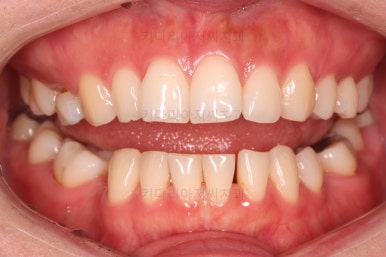

임플란트 보철까지 잘 세팅이 된 후 마무리 하게 되었습니다.

임플란트까지 잘 들어간 후 마무리 했고요.

결손공간 없이 상하좌우 모두 같은 갯수의 치아로 치료가 잘 종료되었습니다.

부산인비절라인 전후 비교해 볼게요.

가장 신경쓰였던 부분이 입매가 양호한 상태에서, 추가 발치에 결손공간까지 폐쇄 해야 하는 상황이어서 입이 더 들어가지나 않을까 하는 점이었는데요.

매우 세심한 컨트롤로 입매는 매우 양호하게 잘 마무리가 되었습니다.

당연히 빈공간에 대한 처리도 잘 되었고요.

얼굴에 대한 중앙선도 잘 마무리 되었습니다.

만약 이 상황에서 좀 더 예쁘게 하고 싶다면 왜소치아를 크기를 키운다면 중앙선의 앞니의 느낌이든 좀더 나아질 수 있었을텐데, 이 부분은 필수가 아니니깐요.

어쨌든 모든 부분에서 인비절라인으로 잘 마무리가 된 환자분이었습니다.

이상 결손치아가 5개 있었고, 비대칭, 유치잔존 환자분을 부산인비절라인으로 교정치료 후 임플란트 2개로 마무리를 한 치료사례였습니다.